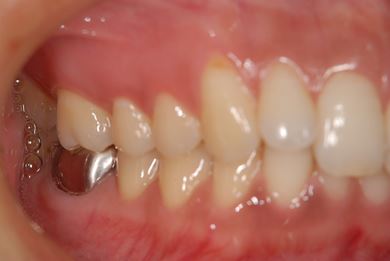

| 性別/年齢 | 女性 / 30歳 | ||||||||||||||||||||||||||||||||

| 主訴 | 銀歯がはずれた奥歯にひびが入っており、抜歯しなければいけないため、インプラントの治療相談を希望。 | ||||||||||||||||||||||||||||||||

| 治療内容 | インプラント1本、メタルボンドセラミック1本 | ||||||||||||||||||||||||||||||||

| 総治療費 | 401,363円 | ||||||||||||||||||||||||||||||||

| 治療期間 | 5ヶ月 |